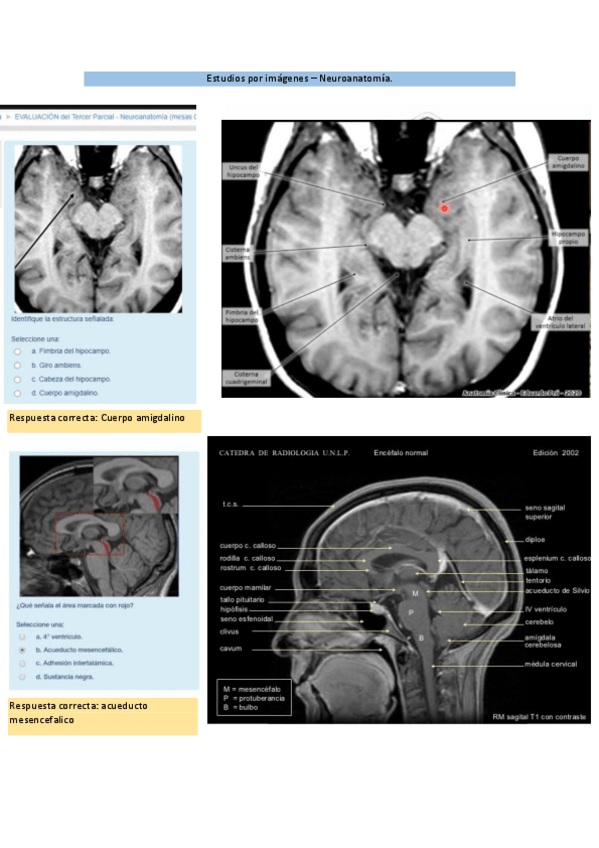

Neuroanatomía

He publicado nuevos examenes de 1º Anatomía: Neuroanatomía

Imagenes-neuro.pdf

Lab-imagenes-neuro-1.pdf